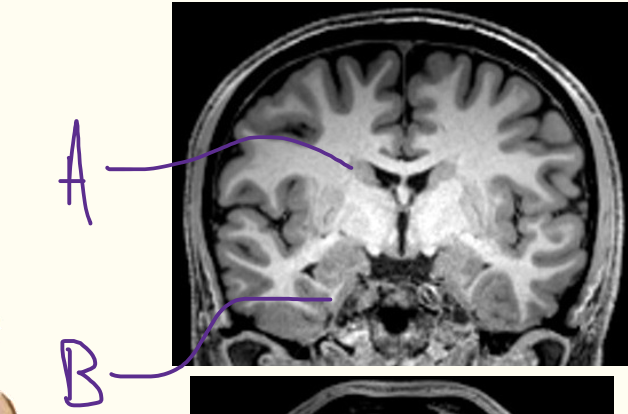

what are structures labelled A & B?

A = caudate nucleus

B = hippocampus

iii) label A-C on diagram

iii) A = lateral ventricles

B = third ventricle

C = interventricular foramen

iii) label structures A-C

iii) A = thalamus

B = fornix

C = third ventricle